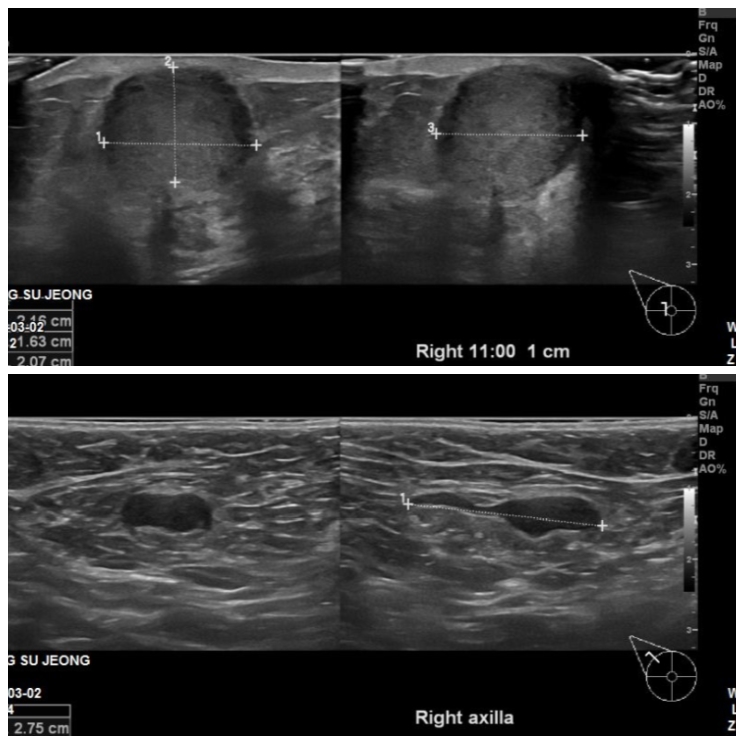

본원에 내원하신 60대 환자분이십니다.

유방초음파 시행후 우측유방 11시 방향에 3.1cm의 혹 조직검사와

우측겨드랑이에 부어있는 림프절을 세침검사시행하였고

침윤성 유관암과 겨드랑이 전이로 진단되었습니다.